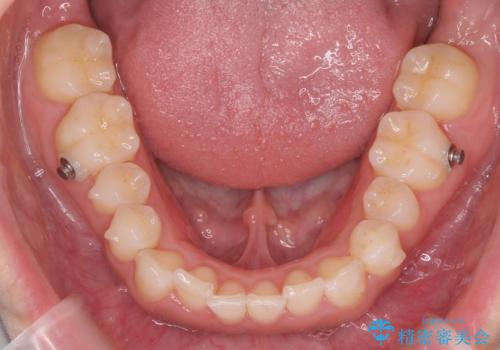

八重歯を非抜歯で マウスピースで治療 奥歯を後ろに下げてすき間を確保

- 八重歯を主訴に来院。

仕事柄ワイヤーが見えるよりはマウスピースで目立たなく歯並びを良くしていきたいとのことでした。

奥歯を後ろに下げてすき間を確保し、八重歯を引っ込めて並べる治療を行いました。

奥歯を後ろに下げるために、矯正用のミニスクリューを使用しています。